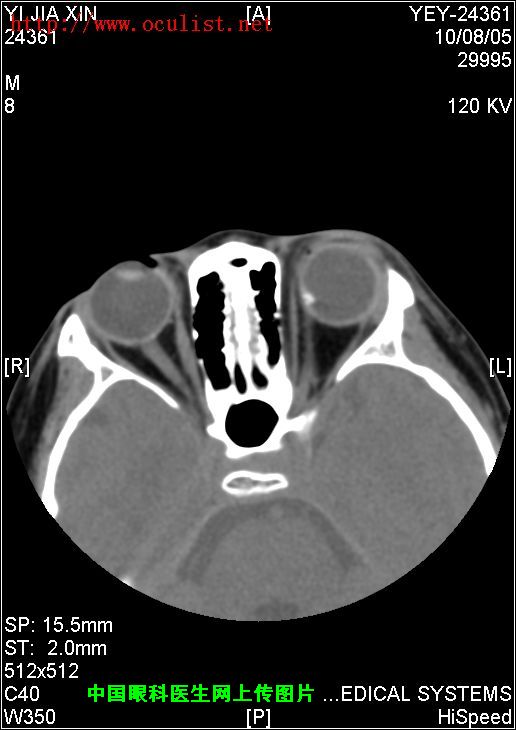

患者男,9岁,发现左眼外斜9年,检查:左眼视力0.01(矫正不应),左眼外斜400,角膜、晶状体未见异常,眼底如下图,CT如下图,RMI暂无,请分析一下该患儿的诊断?

眼底图和CT片: